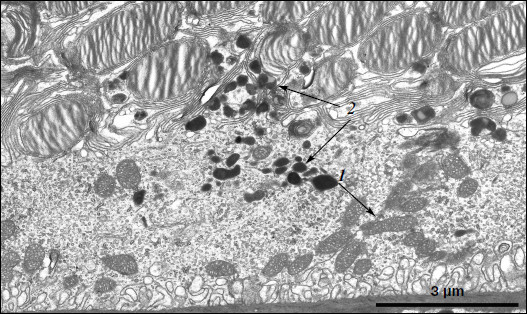

Figure 3

Fig. 3. Ultrastructural peculiarities of cytoplasmic inclusions – the layer of electron-dense structures. a) Lipofuscin granules. Arrows: 1) amorphous stroma substance; 2) aggregates of small osmiophilic granules; 3) osmiophobic regions or spherules; 4) electron-dense layer surrounding osmiophobic regions. b) Electron-dense structural formations. Arrows: 1) single-layer membrane; 2, 3) granules of different density; 4) a granule with heterogeneous ultrastructure; 5) a region of fibrillar structures; 6) closed-type layers of concentric membranes.

Ultrastructure of pigment epithelium cells. Pigment epithelium of Wistar cells (Fig. 1) consists of a layer of cells in the apical part of which there are fine strands of vertical extended cytoplasm offshoots surrounding rod outer segments. Phagosomes, debris of photoreceptor outer segments that underwent phagocytosis by pigment epithelium, sometimes can be seen in these cytoplasm offshoots near rod cell bases (Fig. 2). The characteristic ultrastructural feature of pigment epithelium is the presence in apical part of the cytoplasm of a layer of electron-dense structures (Fig. 1). As a rule, these structures are considered in the literature to be lipofuscin granules [12, 13]. We found in the apical part of pigment epithelium cells of 11-month-old Wistar rats practically continuous homogeneous layer of electron-dense structures – cytoplasmic inclusions (Fig. 1). Ultrastructural analysis of this layer showed that it contains morphologically extremely heterogeneous structures. First of all, these are lipofuscin granules. On the electron-microscopic photograph of the pigment epithelium region (Fig. 3a) arrows point to ultrastructure of two lipofuscin granules in the case of different section direction. It is seen that ultrastructure of lipofuscin granules corresponds to classical concepts. They can have round, oval, or polygonal shape depending on the section plane. Each granule is surrounded by a single-layer membrane contains moderately contrasting amorphous stroma substance (arrow 1) and aggregates of osmiophilic small granules (arrow 2). Oval osmiophobic regions or spherules (arrow 3) restricted by a layer of smallest particles of high electron density (arrow 4) can be seen within the amorphous substance. Besides, this layer of electron-dense structures includes large formations of variable size, shape, and internal arrangement. Figure 3b shows different structure of these formations. They are restricted by a single-layer membrane (arrow 1), contain granular stroma substance of different density in separate granules (for comparison arrows 2 and 3 point to granules of different density), and have heterogeneous ultrastructure along their length. Thus, arrow 4 in Fig. 3b points to a granule containing a region of fibrillar structure (arrow 5) as well as the close-type layers of concentric membranes restricting the space filled by the granular substance of electron density lower than that of stroma (arrow 6). We suppose that different ultrastructure of these formations is due to the fact that they are mutually transient structures, because various transient stages can be detected in their internal arrangement.